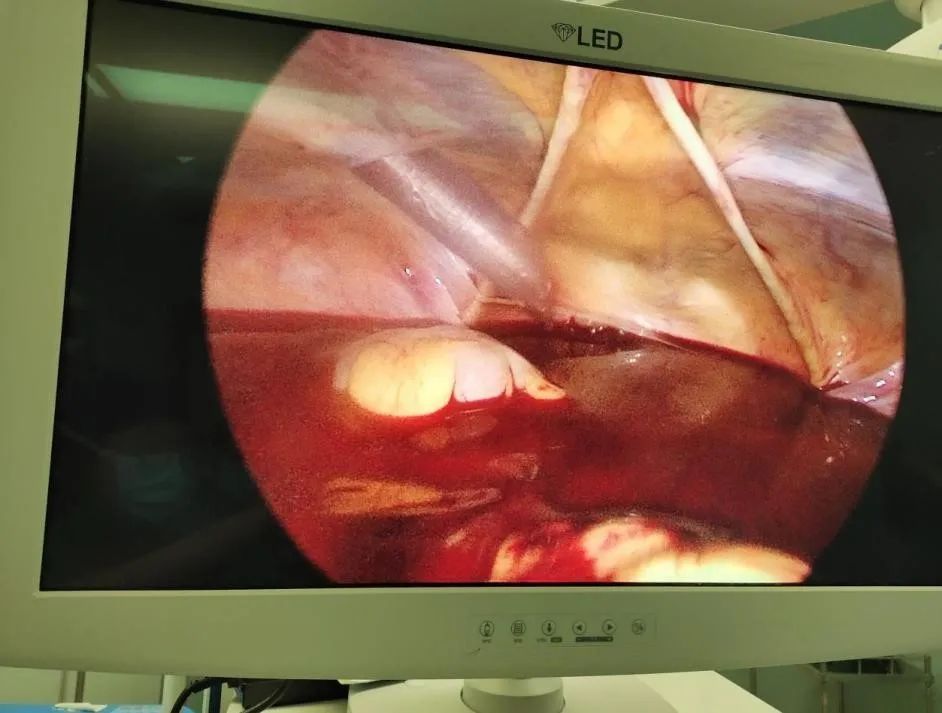

现场由妇产科丘瑾主任、妇科陈敖峥医生坐镇,值班组医生周跃华、陈丹妮组织。当腹腔镜镜头进入腹腔的一刹那,可以清楚的看到子宫和卵巢都浸泡在血液之中。小心翼翼吸出部分血液后,医生仔细地透过镜头找寻着每一处可能的出血口。终于,在右侧卵巢表面发现了一个小破口。至此,大家都暗暗松了一口气……

(腹腔镜下见小周腹腔内大量出血)